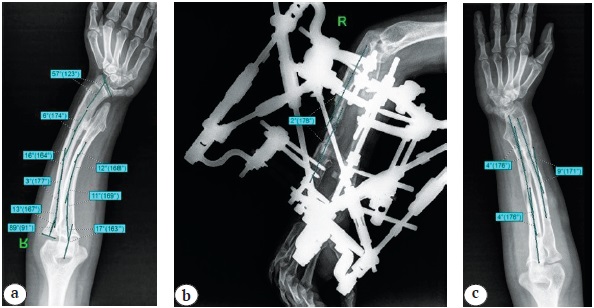

При лучевом обследовании всем пациентам выполняли цифровые рентгенограммы предплечий в двух стандартных проекциях (переднезадняя и боковая). Оценку полученных данных цифровой рентгенографии осуществляли до, после операции и в отдаленном периоде наблюдения с учетом общепринятых референтных линий и углов для костей предплечья [17] (рис. 1).

Рис. 1. Референтные линии и углы для костей предплечья [17]

Figure 1. Reference lines and angles for the forearm bones [17]

- угловые деформации костей предплечья отсутствовали или их величина не превышала 5° (от нормальных референтных значений) (рис. 8);

Рис. 8. Рентгенограммы правого предплечья: а — до операции; b — после выполненной коррекции деформаций локтевой кости (с наложенной навигационной системой Орто-СУВ); c — после снятия АВФ (через 9 мес. после операции)

Figure 8. X-rays of the right forearm: a — before surgery; b — after correction of ulnar deformities (with the Ortho-SUV navigation system applied); c — after removal of the external fixation device (9 months after surgery)